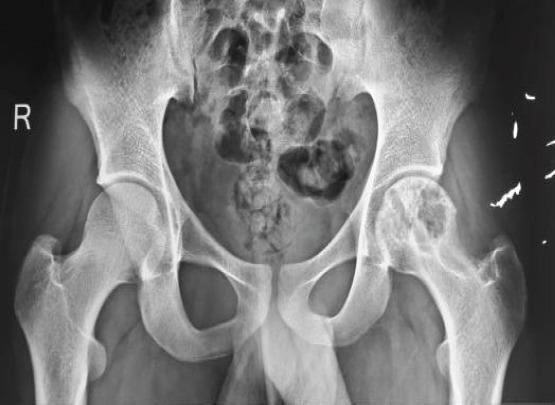

An 18-year-old male patient presented with the left groin pain and terminal restriction of hip movement for 1 year duration. The patient underwent open biopsy and histopathological examination of tissue specimen revealed hydatid cyst. The patient was started on albendazole and after 3 months, surgical curettage and removal of cysts were performed with application of bone cement. At 8 years follow-up, the patient is asymptomatic and doing well.

一名18岁男性患者,左侧腹股沟疼痛并伴有髋关节活动终末受限1年。患者接受了开放活检,组织标本的组织病理学检查显示为包虫囊肿。患者开始服用阿苯达唑,3个月后进行了手术刮除并应用骨水泥去除囊肿。随访8年,患者无症状,恢复良好。